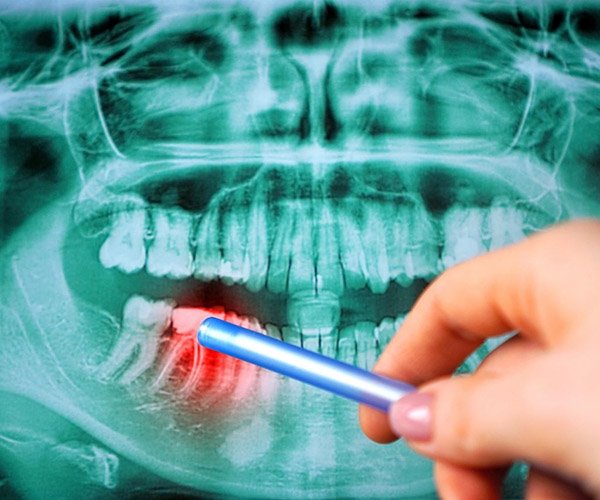

Góckeresés

A fogászatban a góckutatás egy olyan diagnosztikai eljárás, ahol az alapos vizsgálat célja a szájüregben található rejtett fertőzési gócok felderítése. Ezek a gócok végső soron olyan krónikus gyulladások, melyek gyakran tünetmentesek ugyan, mégis kihatással lehetnek az egész szervezetre. A gócok kialakulásának leggyakoribb oka a nem megfelelően kezelt fogászati betegség (fogszuvasodás, gyulladás, foghúzás után bent maradt részecske). A kezeletlen gócok baktériumok és más kórokozók forrásai lehetnek, amelyek bekerülhetnek a véráramba, ezáltal károsíthatva a szervezet más részeit. A fogászati góc kezelése általában fogorvosi beavatkozást igényel.

Számos dolog okozhat gócot a szervezetünkben. Például az előbújni nem tudó bölcsességfogak is góccá alakulhatnak vagy a fogágy betegségek is gyakorta okozhatják.

Góckeresés Góckeresés

Góckutatás (röntgen+konzultáció) 28.000 Ft